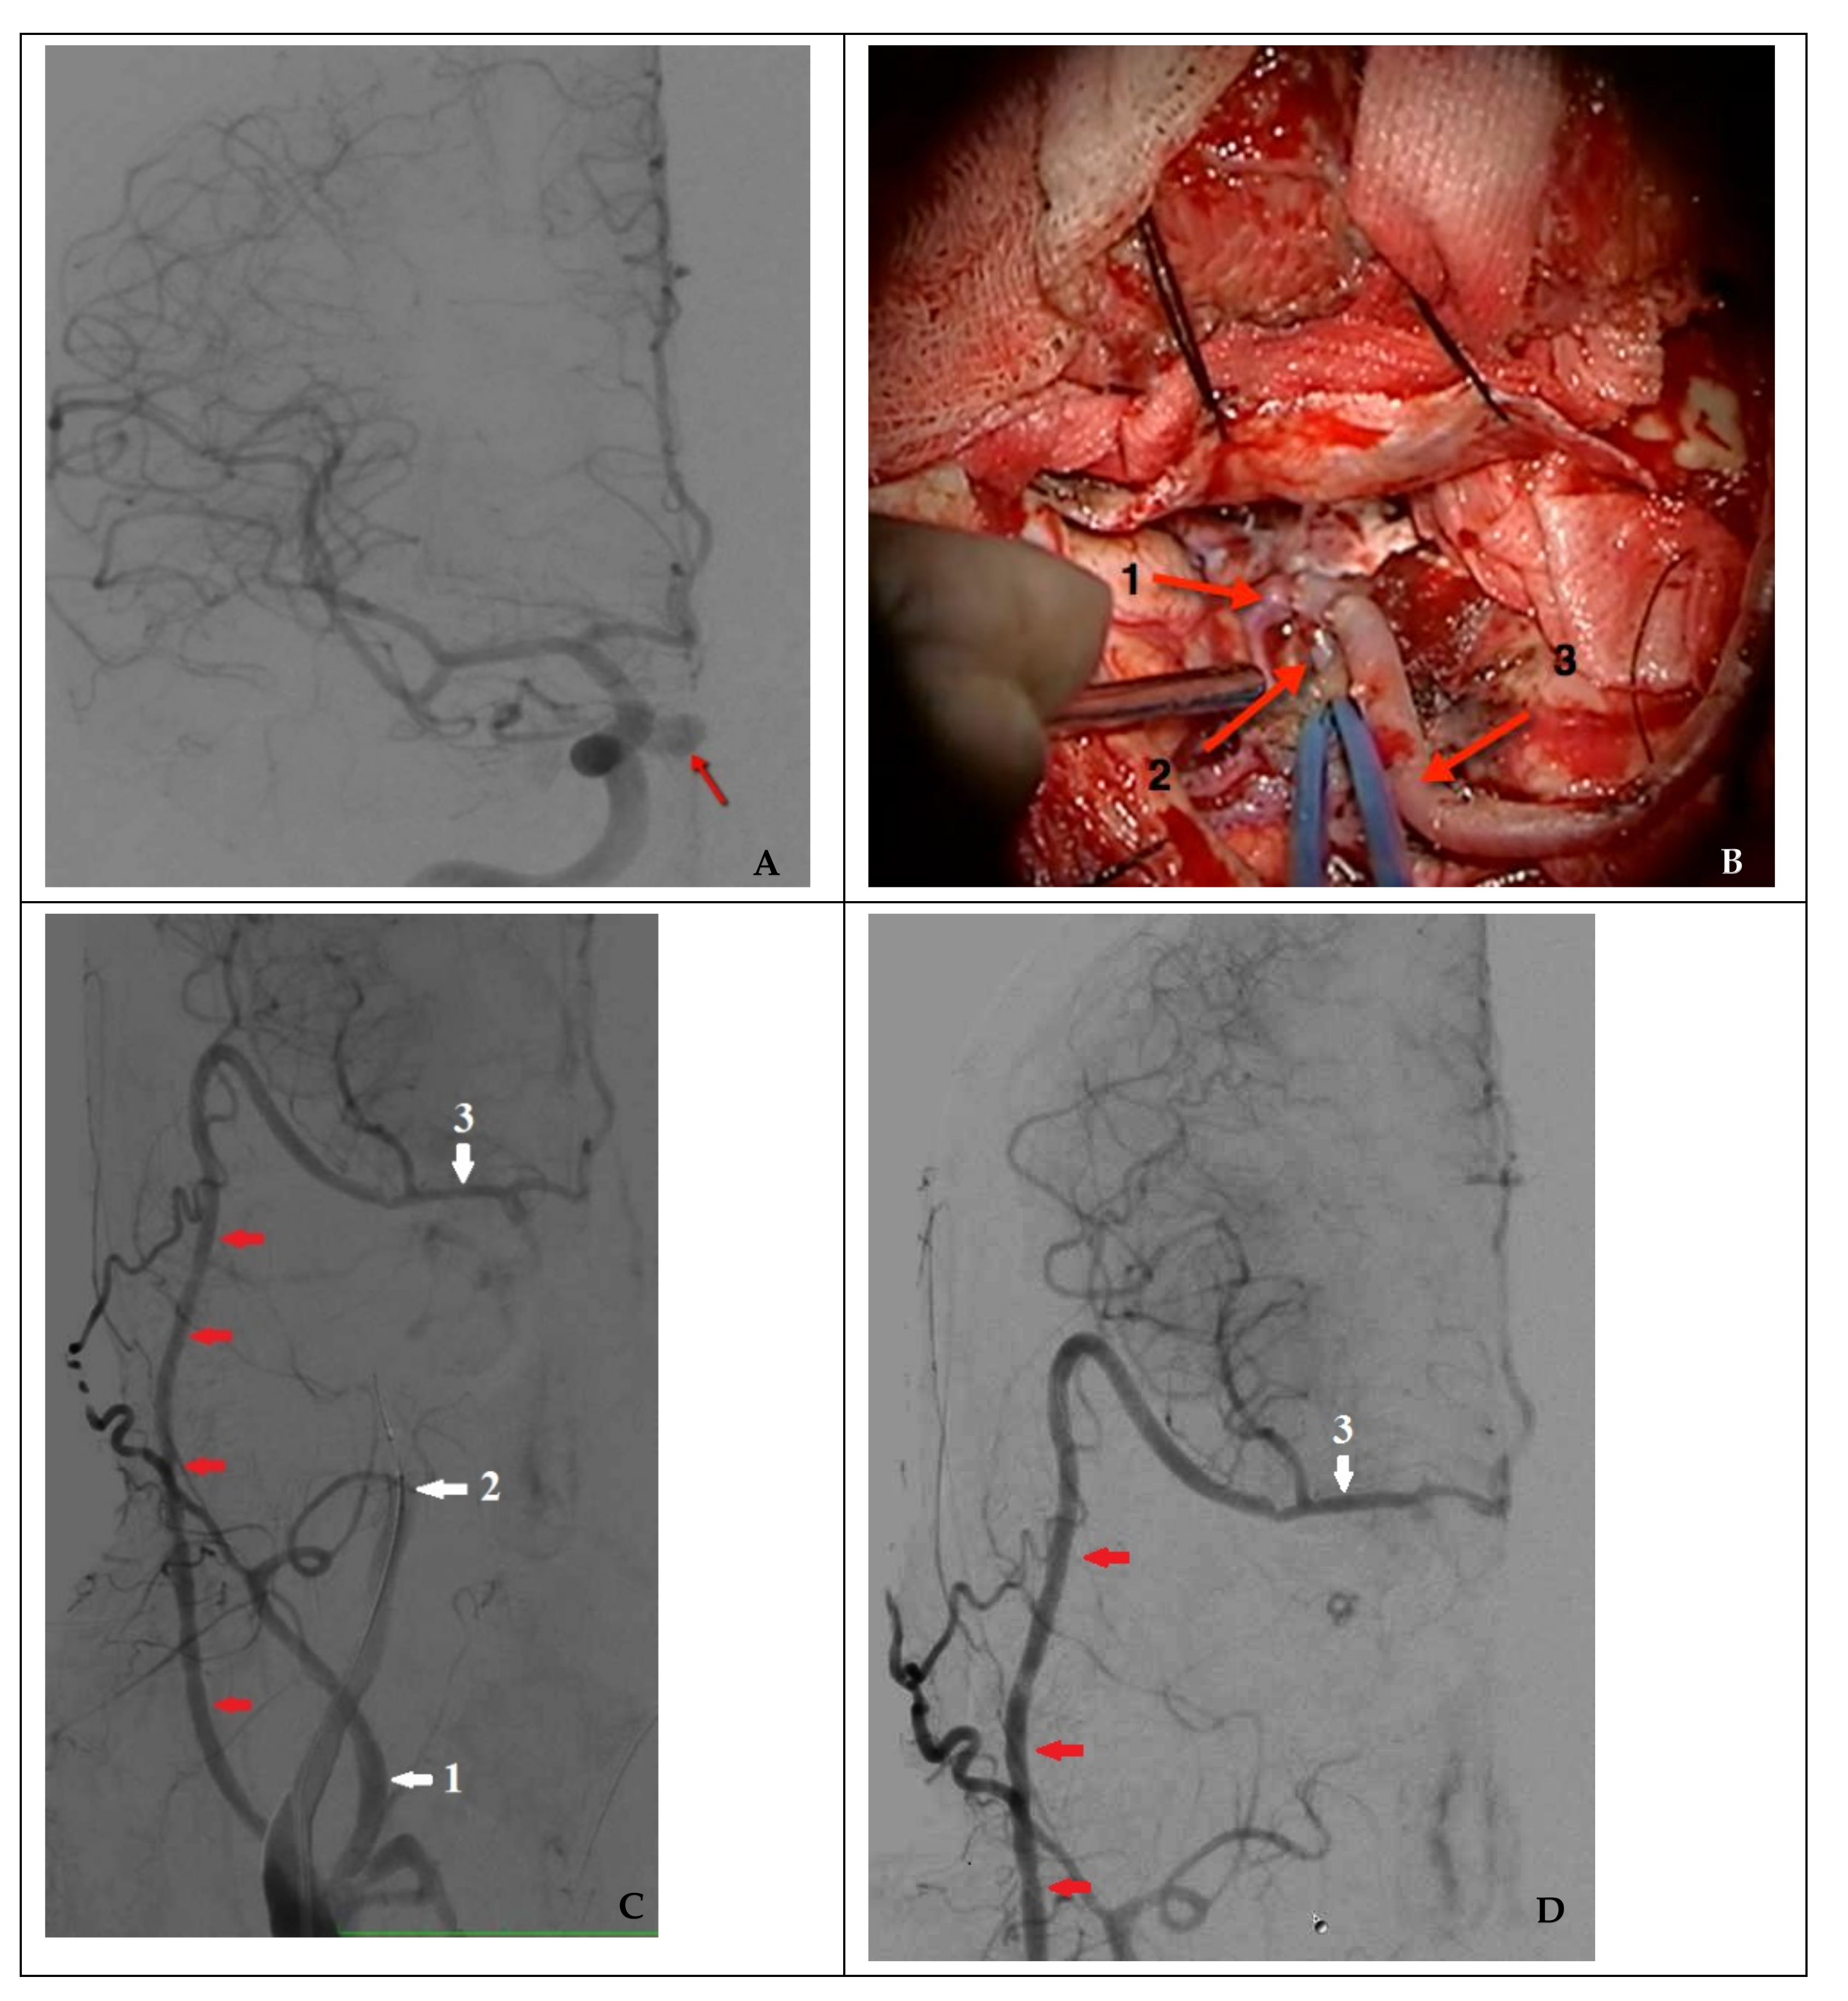

Figure 5. Combined treatment in a case of nonsufficient circulation (clinical case 8). (A) Angiography of the right ICA (the arrow indicates a false aneurysm), (B) view of a high-flow bypass with right MCA M2 segment bifurcation (1: frontal branch of M2; 2: distal sections of the temporal branch of M2; and 3: radial artery as the graft), (C) functioning high-flow bypass (indicated by red arrows) during a temporary test ICA occlusion, and (D) control angiography after endovascular occlusion of a false aneurysm and the injured right ICA (1: external carotid artery; 2: internal carotid artery occluded by a balloon; and 3: middle cerebral artery).

In the case of nonsufficient collateral circulation, the approach to closing the defect required maintaining the blood flow in the basin of the injured artery (reconstructive surgery) or replacing the blood flow (bypass) in the MCA basin on the ipsilateral side: in one case, the patient underwent a stent-graft procedure (Figure 4), and one patient underwent a high-flow bypass followed by ICA occlusion using microcoils (Figure 5).

A critical factor in choosing bypass surgery is the preoperative assessment of potential collateral circulation. A low-flow bypass between the branches of the superficial temporal and middle cerebral arteries may not fully compensate for the deficiency of cerebral circulation in the occluded ICA basin, leading to severe ischemic complications [1,8,18]. Hence, high-flow bypass surgery is indicated. In a study by Rangel-Castilla et al. [19] of eight patients with ICA injury, large-caliber extracranial-to-intracranial bypasses with proximal MCA branches were performed on the side of occlusion without severe ischemic complications.